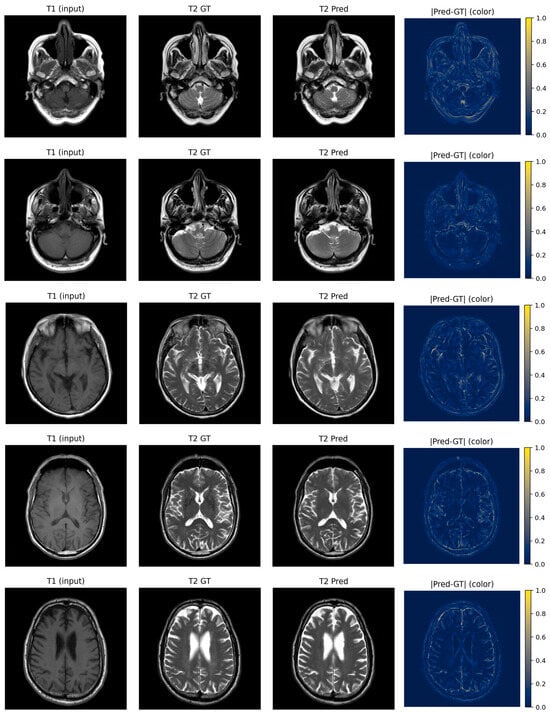

Bidirectional T1–T2 Brain MRI Synthesis Using a Fusion U-Net Transformer for Real-World Clinical Data

Obtaining multiple MRI contrasts for each patient prolongs scan acquisition time, increases healthcare costs, and may not always be feasible due to patient specific constraints. Deep learning-based MRI contrast synthesis offers a potential solution, yet most existing approaches are evaluated on preprocessed public benchmarks that do not reflect real-world clinical variability. In this study, we propose a fusion U-Net transformer framework for bidirectional T1-weighted ↔ T2-weighted brain MRI synthesis trained and evaluated exclusively on retrospectively acquired clinical data. The proposed architecture integrates multiscale convolutional feature extraction with axial attention mechanisms and a transformer bottleneck for efficient global context modeling. A fusion refinement block is incorporated to mitigate skip connection artifacts. An adversarial training strategy with the least squares GAN objective and a hybrid loss combining L1 reconstruction and structural similarity (SSIM) is employed to promote both pixel-level accuracy and perceptual fidelity. The model is evaluated using SSIM and PSNR metrics alongside qualitative expert assessment conducted by two board-certified radiologists. For both synthesis directions, the framework achieves competitive quantitative performance against baseline models under the challenging conditions of clinical data. Expert evaluation confirms high anatomical fidelity and clinically acceptable image quality across both synthesis directions. These results indicate that the proposed framework represents a promising approach for multi-contrast MRI synthesis in clinically heterogeneous data environments. Full article

Figure 1